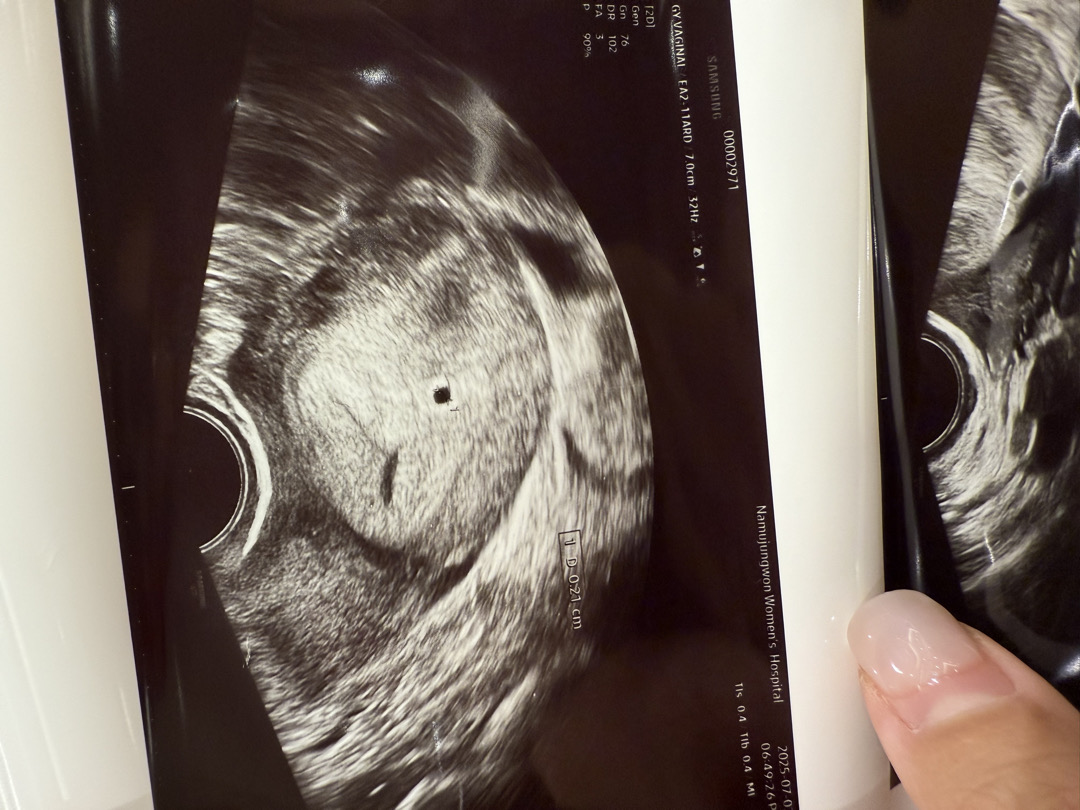

5주차 초음파

저번주 월요일에 아기집 0.2cm 확인했습니다! 네이버 주차 계산기로 했을땐 5주찬데 의사샘은 4주차라고 하시더라구요~ 그리구 6일 지났는데 잘 있는지 너무 너무 궁금해요🥹 아무런 증상이 없어서 불안한 느낌도 있구요 .. 원래는 2주뒤에 와서 심장소리 듣자하셨는데.. 오늘 가서 초음파 확인해봐도 될까요?.. 너무 유난일까요🥹 만약 오늘 가서 아기집 커져있으면 잘 크고있는거겟죠?!